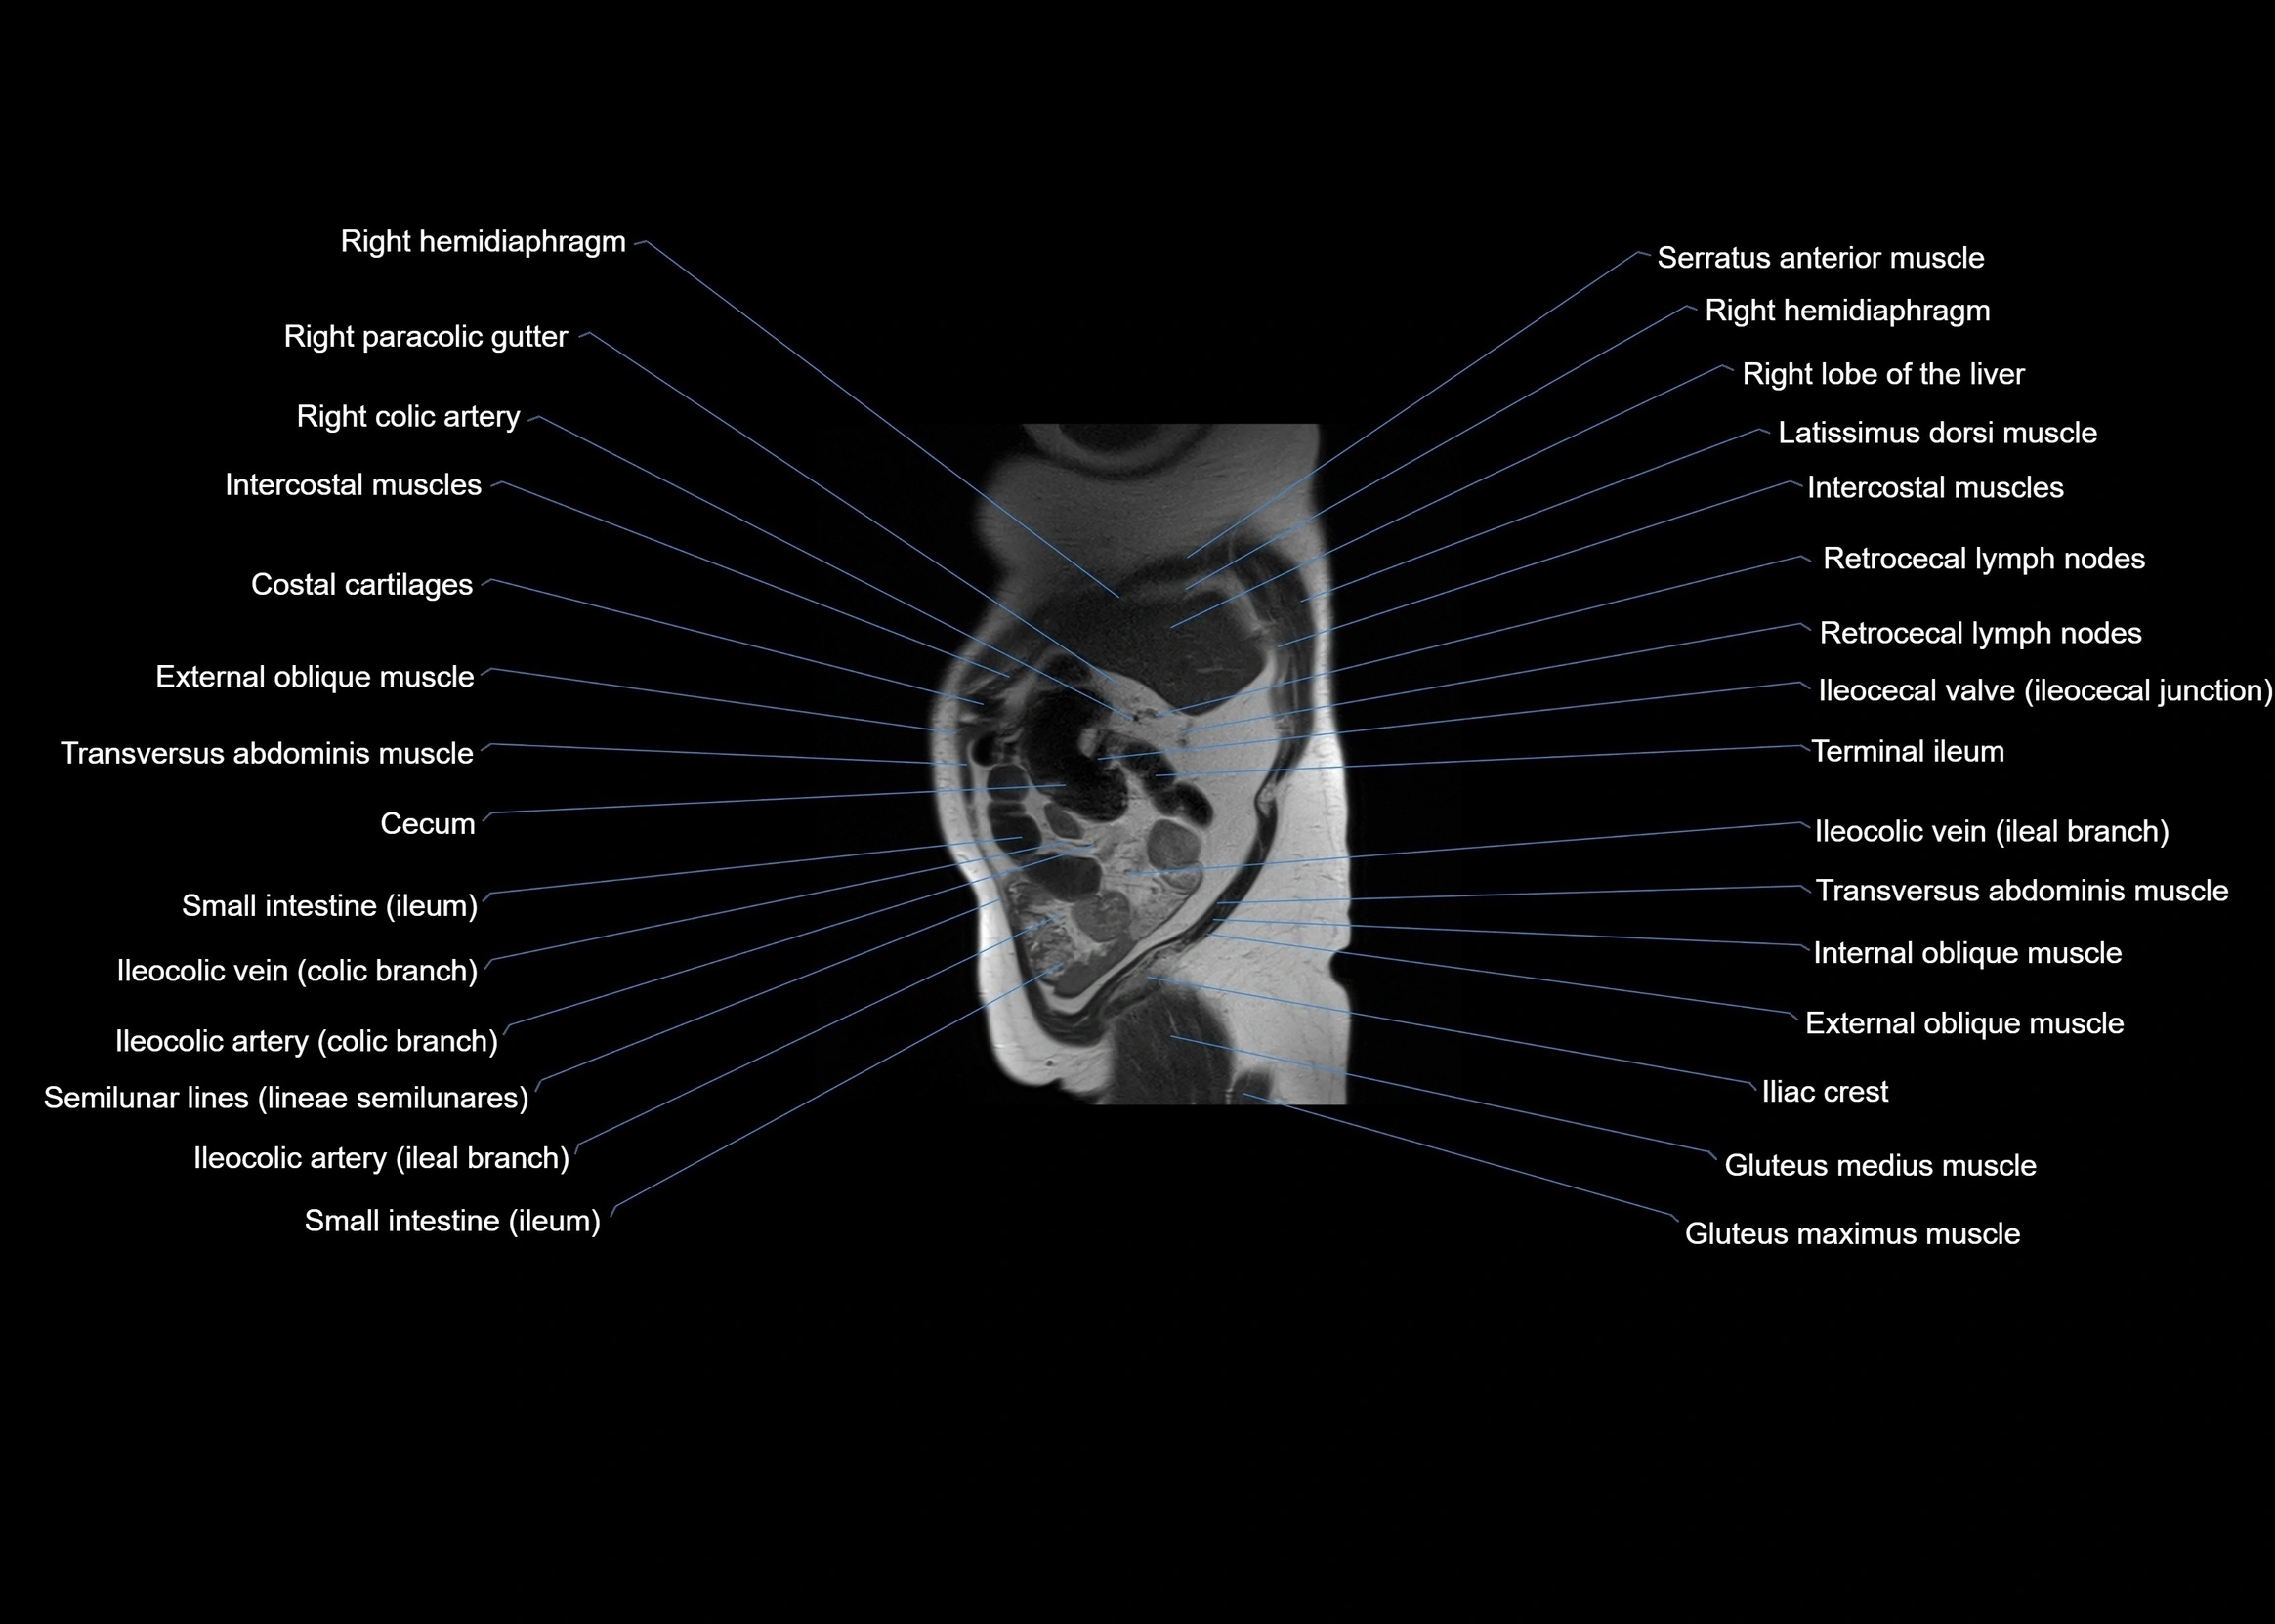

- Cecum

- Ileocaecal valve (ileocecal junction)

- Ileocolic artery

- Ileocolic artery colic branches

- Ileocolic artery ileal branches

- Ileum

- Right colic artery

- Right paracolic gutter

- Terminal ileum